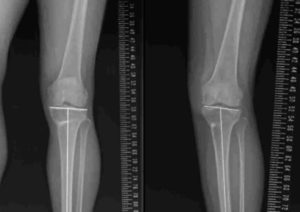

3. Double level osteotomy(DLO)

4. 膝周囲骨切り術2-2